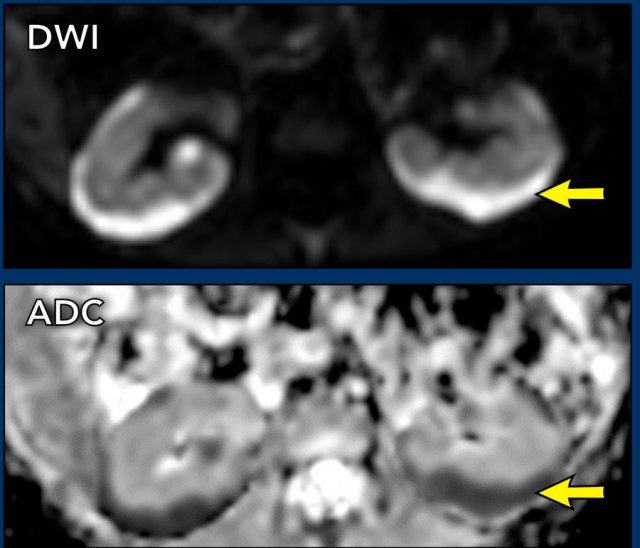

Clear cell sarcoma of the kidney

Clear cell sarcoma of the kidney is rare, approximately 3% of pediatric renal tumors.

The 5-year survival rate is around 80% but it is worse in children below one year of age.

The tumor has a propensity to metastasize to the bone.

The combination of a renal tumor and bone metastases should suggest to the diagnosis of a clear cell sarcoma.

The imaging findings are non-specific, but suggestive features are that these tumors are generally homogeneous with limited diffusion restriction.

video

A ten-month-old boy presented with an abdominal mass. Ultrasound demonstrated a tumor in the right kidney. This is better shown on MRI. The remnant of the kidney has a dilated collecting system.

On ADC images there is limited diffusion restriction.

Histopathology showed a clear cell sarcoma of the kidney.

The tumor was thought to be a Wilms tumor, because of the limited diffusion restriction, but pathology showed a clear cell sarcoma of the kidney.